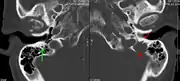

A CT of the brain revealed a lytic lesion in the left temporal bone (right side of image), and petrous temporal bones involving the mastoid segment of the facial nerve canal. Red arrows: lesion; green arrow: normal contralateral facial nerve canal. The lesions are consistent with a myeloma deposit.

The diagnostic examination of a person with suspected multiple myeloma typically includes a skeletal survey. This is a series of X-rays of the skull, axial skeleton, and proximal long bones. Myeloma activity sometimes appears as "lytic lesions" (with local disappearance of normal bone due to resorption) or as "punched-out lesions" on the skull X-ray ("raindrop skull"). Lesions may also be sclerotic, which is seen as radiodense.[70] Overall, the radiodensity of myeloma is between −30 and 120 Hounsfield units (HU).[71] Magnetic resonance imaging is more sensitive than simple X-rays in the detection of lytic lesions, and may supersede a skeletal survey, especially when vertebral disease is suspected. Occasionally, a CT scan is performed to measure the size of soft-tissue plasmacytomas. Bone scans are typically not of any additional value in the workup of people with myeloma (no new bone formation; lytic lesions not well visualized on bone scan).